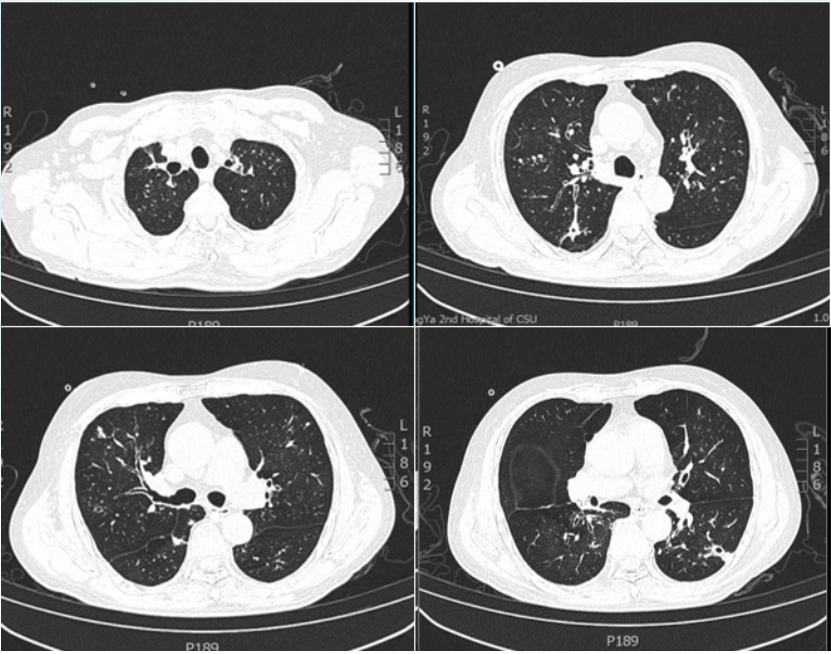

5月16日复查胸部CT:肺部病变明显好转空洞变薄,部分结节消失(图4)

图片

4  复查胸部CT(2023-05-16)